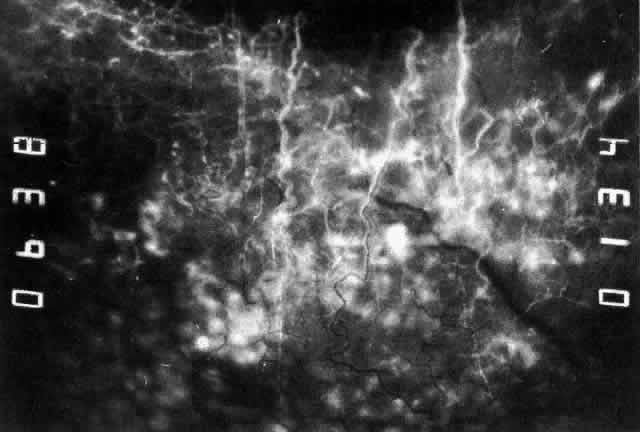

The object of slit lamp examination is to determine the depth and nature of scleral and episcleral conditions and the presence of corneal changes. The changes seen are drawn in the records. With the use of diffuse light with a neutral density filter, the vascular networks of both eyes are examined in detail to determine the layer in which the vessels show maximum congestion, the infiltration of episcleral tissues, and the edema of sclera, episclera, or subconjunctival space. Slit lamp examination is also used to ascertain the nature and depth of any corneal changes; the presence of scleral edema (for which it may be necessary to blanch the superficial tissues with epinephrine 1:1000 or phenylephrine 10%); the nature of any episcleral infiltration or mass; and the presence of cells in the anterior chamber or vitreous and posterior synechiae. The red-free (green) filter is extremely valuable in confirming the areas of maximum congestion and whether any areas are totally avascular. Because this is an important physical sign and is easily missed, examination in red-free light should be routinely performed. The green light brings the vessels into very sharp contrast with the background and enables the position of maximum inflammation to be determined with certainty. It also enables the paths and configurations of the vessels to be followed and will show lymphocytic infiltration of the episcleral tissue as yellow spots; this often indicates that the condition is more extensive than previously supposed (Fig. 8).

Fig. 8. Examination in red-free light. Blood vessels brought into sharp contrast reveal areas of lymphocytic infiltration in episcleral tissues, in this case due to herpes simplex virus.